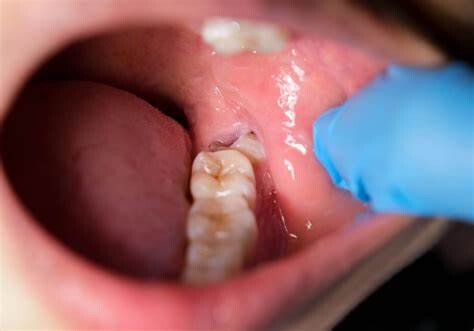

In some cases, jaw pain on one side can indicate underlying oral health problems. Some common issues that cause jaw pain are cavities, an abscessed tooth, gum disease, tooth decay, growth of wisdom teeth, missing or crooked teeth, and clenching or grinding your teeth.

Tooth decay

As tooth decay progresses, it can reach the softer inner layers of the tooth, called dentin and pulp, resulting in sensitivity to hot, cold, or sweet foods and drinks and eventually leading to a toothache. If left untreated, tooth decay can result in an abscess, a painful infection at the root of the tooth that can cause severe pain and swelling. Adhering to your routine dental check-ups, practicing good oral hygiene, and eating a healthy diet can help prevent tooth decay and the resulting toothache.

The fully impacted or the partially impacted wisdom teeth are at greater risk of tooth decay, than other teeth. This usually happens, because of the location of the wisdom tooth, especially towards the back of the mouth, which is hard to clean. Moreover, since it lies at the back of the mouth, there are chances of food getting easily trapped between the gums and the tooth, promoting the growth of bacteria.